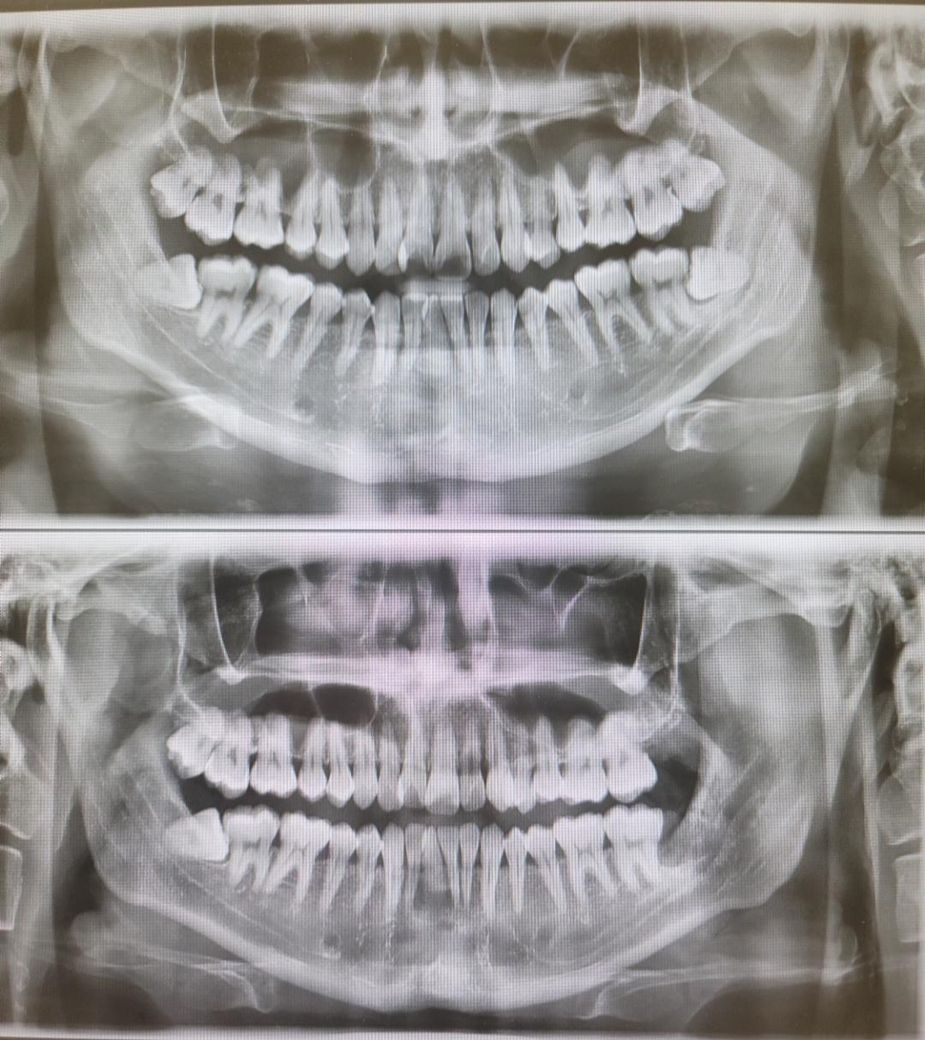

치아 시림 증상 질문 답변 부탁 두립니다 ( 엑스레이 첨부)

제가 17년전쯤 운동하다 얼굴 입쪽을 크게 다친적이 있는데

그때 상악 왼쪽 앞니가 흔들릴 정도의 충격을 받아 치과가서 응급조치만 받고 나온적이 있습니다

이를 두드려 보거나 가끔 컨디션이 안좋으면 앞니에 살짝 시린통증이 오는거 말곤 괜찮다가

이번에 왼쪽 사랑니 2개를 뽑고 나니 왼쪽 치아 전체가 조금씩 시리면서 앞니 증상도 조금 더 심해졌습니다

그동안 치과가서 엑스레이를 찍어봐도 의사선생님이 왼쪽앞니에 대한 말씀은 전혀 없으셔서

여기서 선생님들의 고견을 듣고 싶습니다

• 1번 째 사진

엑스레이 상으로는 크게 문제가 잇어 보이진 않습니다. 잇몸이 안좋아서 그럴수도 잇고 교합때문에 치아가 예민해져서 그럴수도 잇을것같습니다.

사랑니를 빼서 앞니에 영향이 갔을 확률은 거의 없고요 앞니 상태와 관련해선 작은 엑스레이 사진을 좀 찍어보면 좋을 것 같습니다